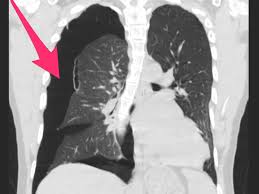

Study Shows Ai Technology Accurately Detects Collapsed Lungs

Study Shows Ai Technology Accurately Detects Collapsed Lungs from www.medicaldevice-network.com